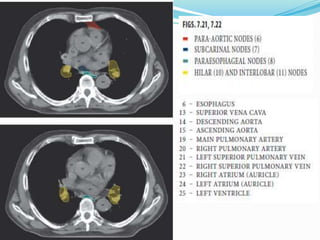

The International Association for the

 14 LN stations reorganized into 7 zones

 Supraclavicular zone

 Upper zone

 AP zone

 Subcarinal zone

 Lower zone

 Hilar zone

 Peripheral zone